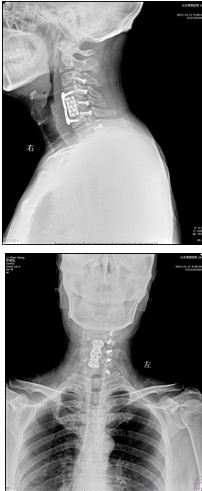

患者,男性,49岁,主因“行走不稳2个月伴右前臂麻木1个月”入院

2月前开始出现双下肢行走不稳,有踩棉花感,行走距离受限。1月前出现右侧前臂及手指麻木感。3周前诊断为“颈椎病”,保守治疗无改善,行走不稳症状加重

影像检查结果:

手术效果:术后当天下肢麻木无力症状即消失,术后1天,上肢麻木无力症状也好转。术后7天离床活动,自觉踩棉花感觉消失,下肢变得有力,可以正常速度上下楼,双手抓握力量明显增强,灵活性好。查体上肢肌力如屈指肌力、小指外展肌力恢复到5级,下肢小腿三头肌肌力恢复到5级。